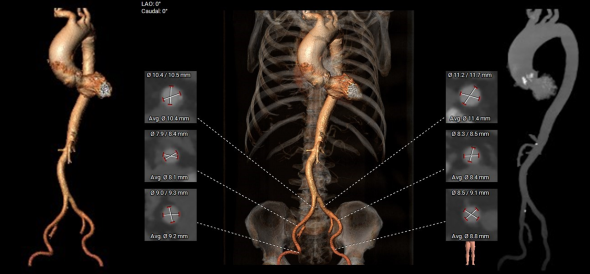

主动脉根部测量

CT特点:Type 0型二叶式主动脉瓣,左右冠不同窦,瓣叶中重度钙化伴增生肥厚,钙化呈偏心性分布;左右冠开口高度可,无冗长瓣叶;近横位心,心室壁肥厚。

瓣上测量

瓣上测量:瓣叶中重度钙化伴增生肥厚,钙化呈偏心性分布,主要分布于瓣叶边缘及前壁交界附着缘。

弓部及入路评估

入路血管: 双侧髂动脉可见明显扭曲,未见明显钙化,入路血管直径良好。